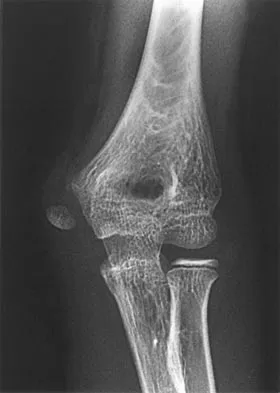

Figure 4a shows the radiograph of a 20-year-old man who has an injury to the right shoulder. Figure 4b shows an arthroscopic view (posterior portal). The arrow points to a

Explanation

The radiograph shows an anterior dislocation of the shoulder. A frequently encountered sequela of this is a compression fracture of the posterolateral humeral head, commonly referred to as a Hill-Sachs defect. The arthroscopic view of the glenohumeral joint visualizes the posterior aspect of the humeral head. In the image, the area devoid of cartilage to the right is the bare area. The indentation seen to the left is a Hill-Sachs defect. Matsen FA, Thomas SC, Rockwood CA, et al: Glenohumeral instability, in Rockwood CA, Matsen FA (eds): The Shoulder, ed 2. Philadelphia, PA, WB Saunders, 1998, pp 611-754.